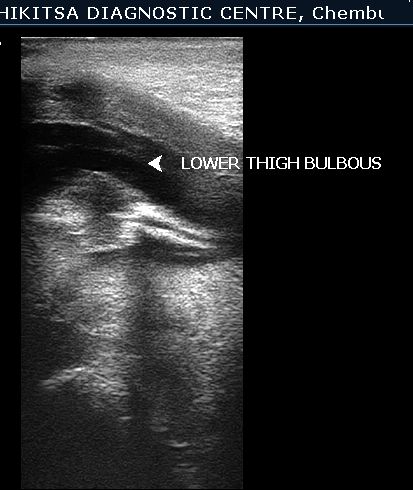

A 23 year old Primigravida was scanned at 15 weeks gestation for the first time. On U/S - she was having severe oligohydramnios. The lower limbs of fetus were found to be fused & proximal portion contained 2 long bones ( Femora ). External genitalia of fetus were not visualised. On colour flow , the fetus was found to have single umbilical artery. Other congenital anomalies could not be ruled out because of severe oligohydramnios & period of gestation at which ultrasound was performed. The patient was referred back to the obstetrician for further management.In view of congenital malformation incompatible with life , MTP was carried out by obstetrician & diagnosis was confirmed.